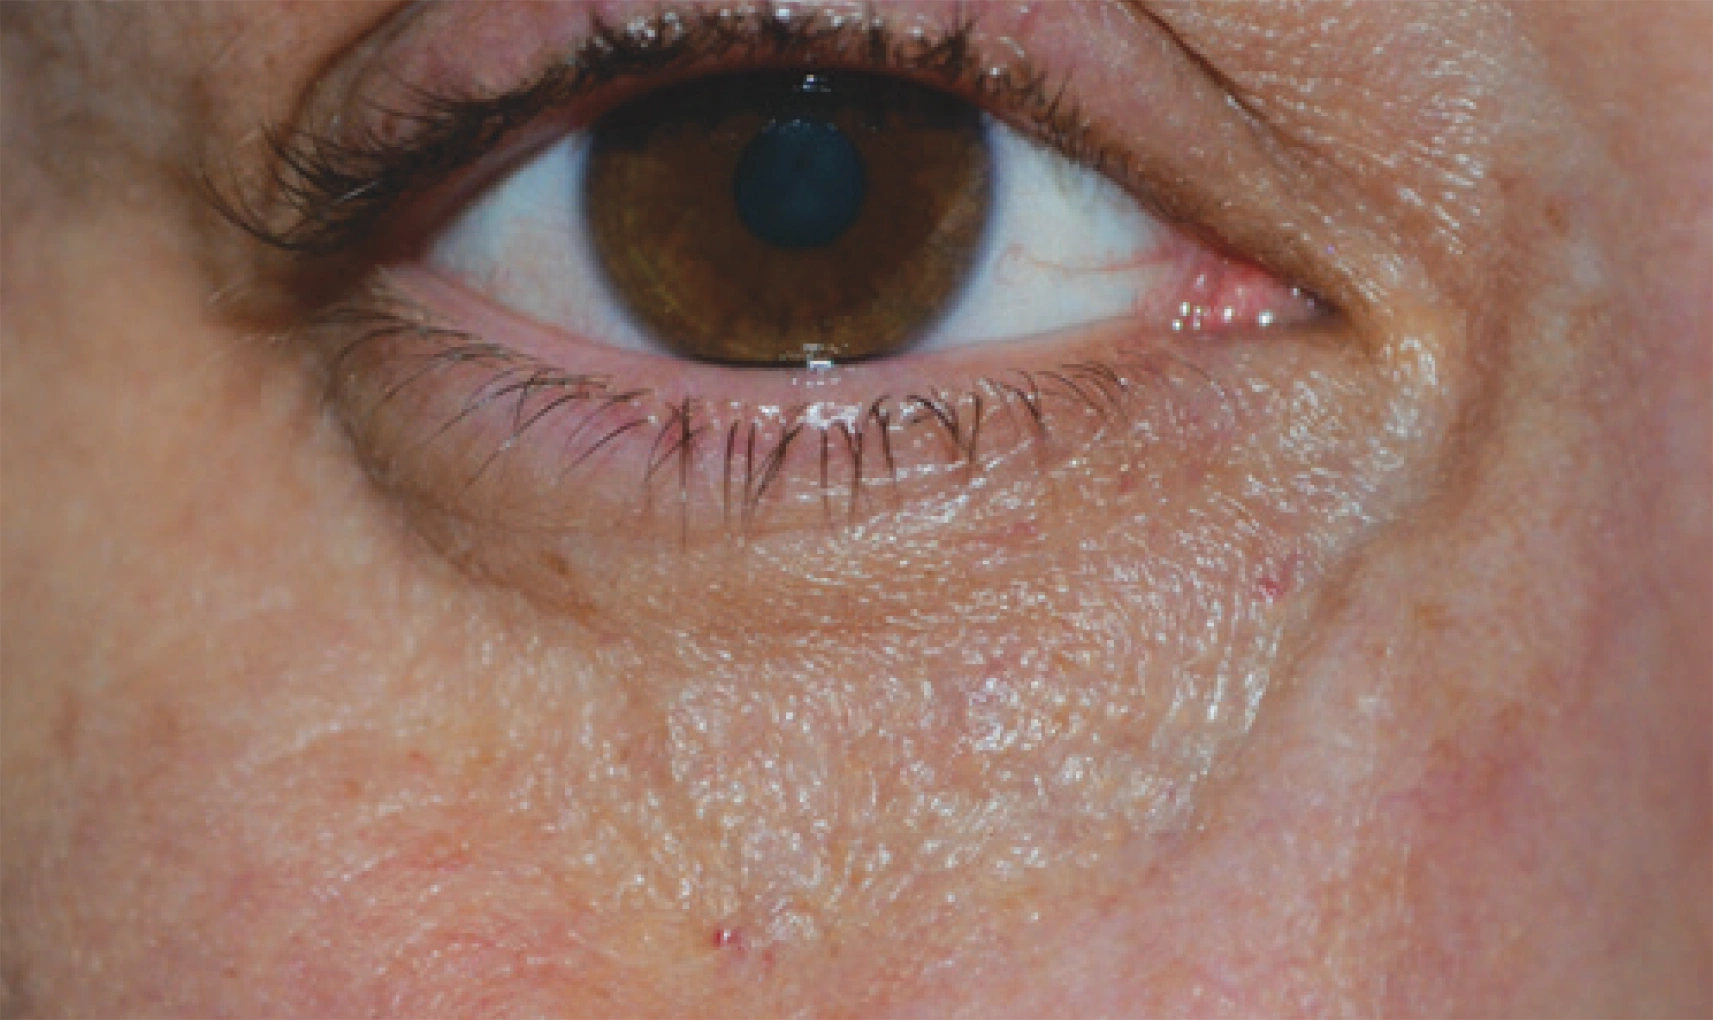

ENDOLIFT® ist eine minimalinvasive Laseranwendung mit dem LASEmaR® 1500, die auf eine Verbesserung der Hautqualität und eine definiertere Gesichtskontur abzielt – ohne sichtbare äußere Verletzungen. Das Verfahren wird in Bereichen angewendet, in denen eine beginnende Hauterschlaffung erkennbar ist, zum Beispiel im Gesicht, am Kinn, am Hals oder im Unterlidbereich.

Bei ENDOLIFT® Verfahren werden sehr feine, flexible Einwegfasern knapp unter der Haut im oberflächlichen Unterhautgewebe platziert. Dafür reicht in der Regel ein kleiner Einstich aus. Je nach Areal und Empfindlichkeit kann eine leichte lokale Betäubung eingesetzt werden, der Eingriff wird jedoch von vielen Patientinnen und Patienten als gut tolerierbar beschrieben.

Nach der Behandlung kann es vorübergehend zu leichten Rötungen, Schwellungen oder Verfärbungen kommen. Diese Reaktionen sind individuell unterschiedlich und klingen in der Regel selbstständig ab. Die meisten Personen können ihre normalen Aktivitäten zeitnah wieder aufnehmen.

Während einzelne Effekte bereits früh sichtbar sein können, entwickelt sich das Ergebnis typischerweise über einen längeren Zeitraum weiter. Das Verfahren kann körpereigene Prozesse, wie eine Verbesserung der Hautstruktur, unterstützen. Wie stark und wie lange diese Effekte anhalten, hängt von individuellen Faktoren wie Hautbeschaffenheit, Stoffwechsel und Lebensstil ab.

Viele Patientinnen und Patienten berichten unmittelbar nach der Behandlung von einem ersten Straffungsgefühl. Dieser frühe Effekt kann sich in den folgenden Wochen verändern. Im weiteren Verlauf können körpereigene Regenerationsprozesse, wie die Neubildung von Kollagen, zu einer graduellen Verbesserung der Hautstruktur beitragen.

Neben der Straffung in der Tiefe kann sich auch das Hautbild an der Oberfläche im Verlauf harmonisieren. Wie lange die Ergebnisse sichtbar bleiben, hängt von individuellen Faktoren wie Hautbeschaffenheit, Stoffwechsel und Lebensstil ab. Falls gewünscht, lassen sich Wiederholungsbehandlungen flexibel planen.